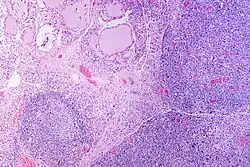

| A micrograph of the thyroid of someone with Hashimoto's thyroiditis | |

Gross morphological changes within the thyroid are seen in the general enlargement, which is far more locally nodular and irregular than more diffuse patterns (such as that of hyperthyroidism). While the capsule is intact and the gland itself is still distinct from surrounding tissue, microscopic examination can provide a more revealing indication of the level of damage.[55] Hypothyroidism is caused by replacement of follicular cells with parenchymatous tissue.[52]

Pathology

Gross pathology of a thyroid with autoimmune thyroiditis may show a symmetrically enlarged thyroid.[5] It is often paler in color, in comparison to normal thyroid tissue, which is reddish-brown.[5]

Microscopic examination (histology) will show lymphocytes (including plasma B-cells) diffusely infiltrating the parenchyma.[55] The lymphocytes are predominately T-lymphocytes with a representation of both CD4+ and CD8+ cells.[5] The plasma cells are polyclonal, with present germinal centers resembling the structure of a lymph node[5] (also called secondary lymphoid follicles, not to be confused with the normally present colloid-filled follicles that constitute the thyroid).[55]

In late stages of the disease, the thyroid may be atrophic.[10] Colloid-filled follicles shrink, and the cuboidal cells that usually line the follicles become Hürthle cells.[5] Fibrous tissue may be found throughout the affected thyroid as well.[5] Severe thyroid atrophy presents often with denser fibrotic bands of collagen that remain within the confines of the thyroid capsule.[55]

Generally, pathological findings of the thyroid are related to the amount of remaining thyroid function — the more infiltration and fibrosis, the less likely a patient will have normal thyroid function.[5] A rare but serious complication is thyroid lymphoma, generally the B-cell type, non-Hodgkin lymphoma.[24]